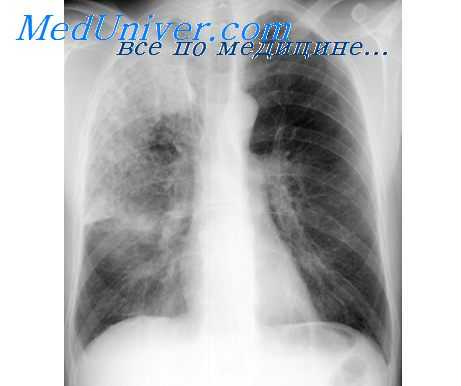

Характеризуя роль нервной системы в развитии воспаления, необходимо остановиться на вопросах сегментарной регуляции воспалительного процесса, а также трофическом влиянии нервной системы на течение воспаления. Данное обстоятельство имеет особое значение при развитии воспалительных заболеваний легких, формировании РДСВ. Показано, что блокирование соответствующих сегментов грудного отдела спинного мозга сопровождается снижением степени выраженности прессорных реакций микрососудов легких и тем самым оптимизацией кислородного обеспечения легочной ткани, снижением концентрации метаболитов, усиливающих деструктивные процессы.